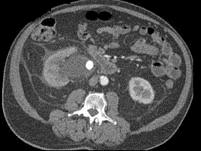

男,27岁,请根据所示图像,选择最可能诊断 ( )A、右肾结石B、右肾钙化C、右侧肾盂结石D、右侧肾盂癌E、右侧肾盂血块

问题 男,27岁,请根据所示图像,选择最可能诊断 ( )

选项 A、右肾结石 B、右肾钙化 C、右侧肾盂结石 D、右侧肾盂癌 E、右侧肾盂血块

答案 C